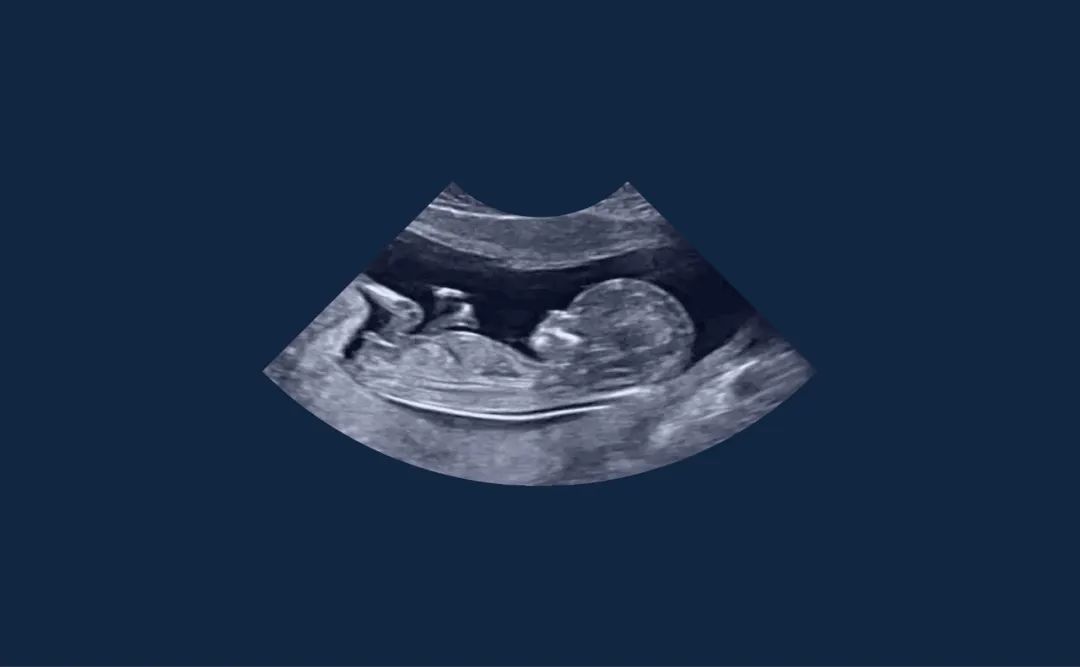

Sonoschool 的目标是培训和支持医生和卫生专业人员进行超声实践,以扩展他们的临床检查并改进他们的诊断。虽然大家都熟悉这种医学成像技术,主要用于妊娠检查,但超声波实际上可以用来检查身体的许多部位。这些设备的小型化和大众化促使 Sonoschool 将超声波扫描仪视为 21 世纪的听诊器,这将有助于医生提高诊断和患者护理的可靠性。通过开设无障碍培训课程,Sonochool 的目标是一方面支持当地超声技术的发展,应对偏远地区超声技术人员的短缺问题,另一方面帮助缓解急诊室的拥挤状况。Graphéine协助他们进行战略定位和创建品牌形象。